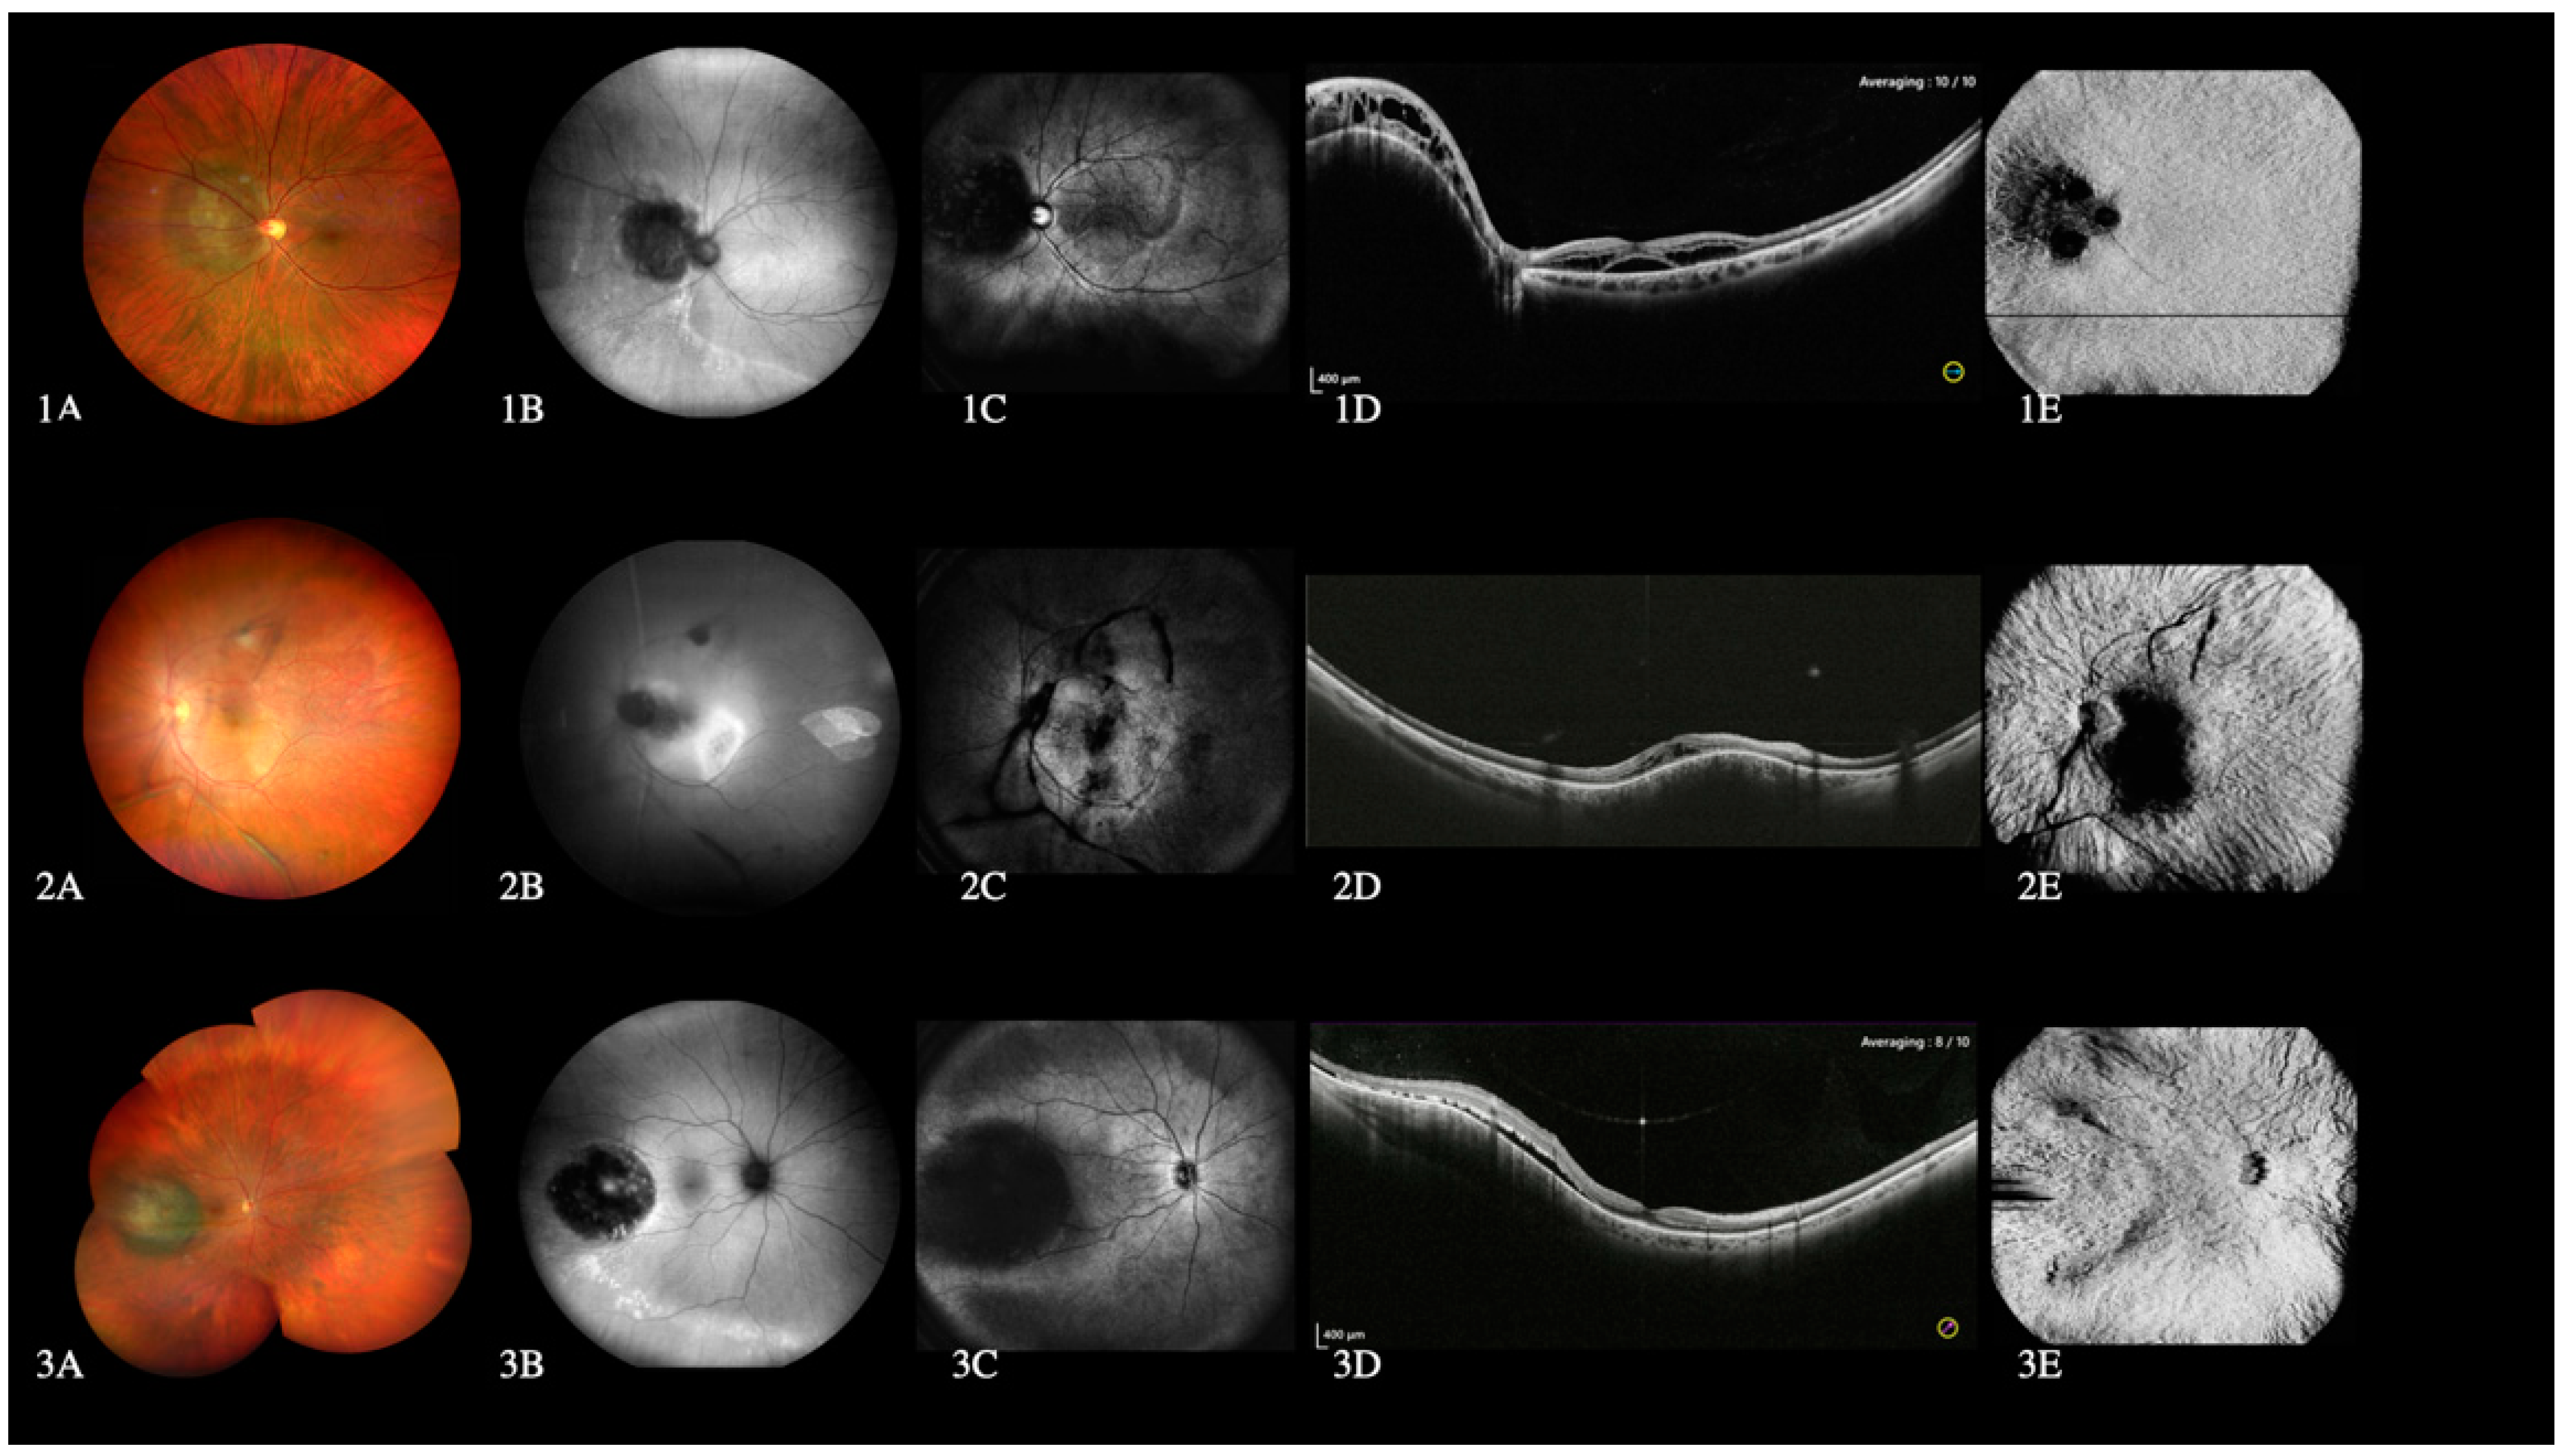

3.4. High Myopia

3.5. Choroidal Lesions